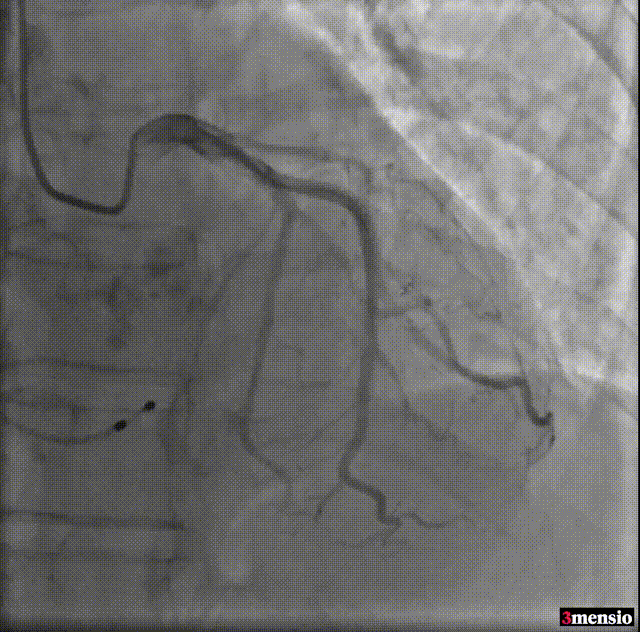

Type-0型二叶瓣,中-重度钙化伴瓣叶增厚,左冠开口高度偏低,右冠开口高度可,左冠瓣叶长度略大于冠脉开口上缘与瓣叶附着缘距离,左室流出道整体呈直筒型,瓦氏窦,窦管交界,升主动脉内径可,左室腔内径可,心室壁增厚,主动脉瓣环与水平面夹角51度,非横位心,主动脉弓距、弓角可 -双侧入路血管走形良好,整体入路条件可

使用沛嘉20mm球囊预扩,预装沛嘉TaurusElite AV23瓣膜,释放高度瓣上0-2mm